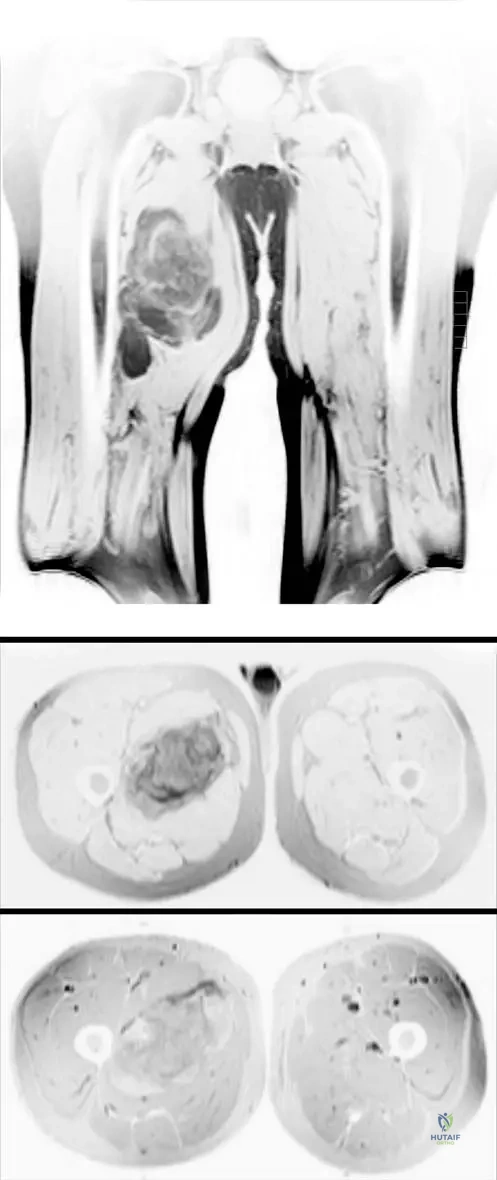

Question 21

A 13-year-old male presents with a painful, rapidly growing mass in his distal femur. MRI images are obtained, as shown. These images demonstrate a large heterogeneous destructive mass in the bone with a large associated soft tissue mass. What is the most likely diagnosis based on these typical findings?

Correct Answer: C

Rationale: The clinical context for Fig. 8.66 explicitly states these MRI images "show typical findings of an osteosarcoma. There is a large heterogeneous destructive mass in the bone with a large associated soft tissue mass." This is a classic presentation for osteosarcoma in this age group. Chondrosarcoma typically presents with chondroid matrix, Ewing sarcoma with a permeative pattern and onion-skin periosteal reaction, osteochondroma is a benign exostosis, and fibrous dysplasia is a benign fibrous lesion.

Question 27

A 14-year-old male is diagnosed with a conventional osteosarcoma of the distal femur. Following initial radiographs and CT, the orthopedic oncologist orders an MRI of the entire femur. What is the MOST critical information this MRI is intended to provide?

Rationale: MRI is the most accurate imaging tool for determining the intraosseous and extraosseous extent of the tumor. It is also important to image the entire bone involved with osteosarcoma to evaluate for skip metastasis. This information is crucial for surgical planning and determining resection margins. Confirming osteoid matrix is done by biopsy. Assessing mineralization is better with CT. Pulmonary metastases are evaluated with chest CT. Differentiating benign from malignant is usually achieved with initial radiographs and biopsy. The image (Fig. 8.66 a–c) shows how MRI clearly delineates the extent of the mass.